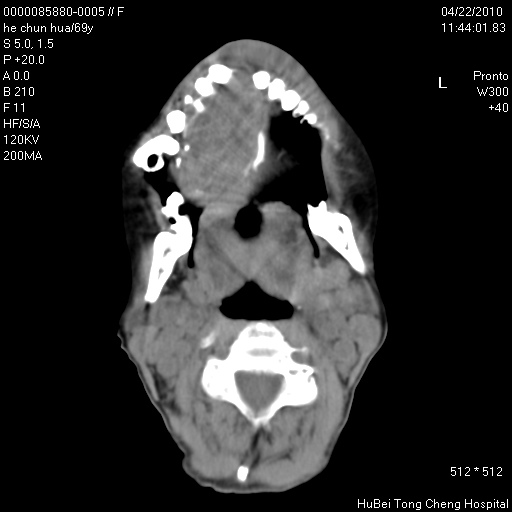

标题: CT25937:女,69Y

硬腭部包块十余年,渐进性增大。

不管以前,现在是恶性占位了

支持硬腭部恶性肿瘤!

硬腭部肿瘤恶变可能。

硬腭占位 恶性可能性大

骨源性肿瘤 造秞细胞瘤

考虑硬腭部肿瘤恶变,gcrg可能,鉴别于gct。